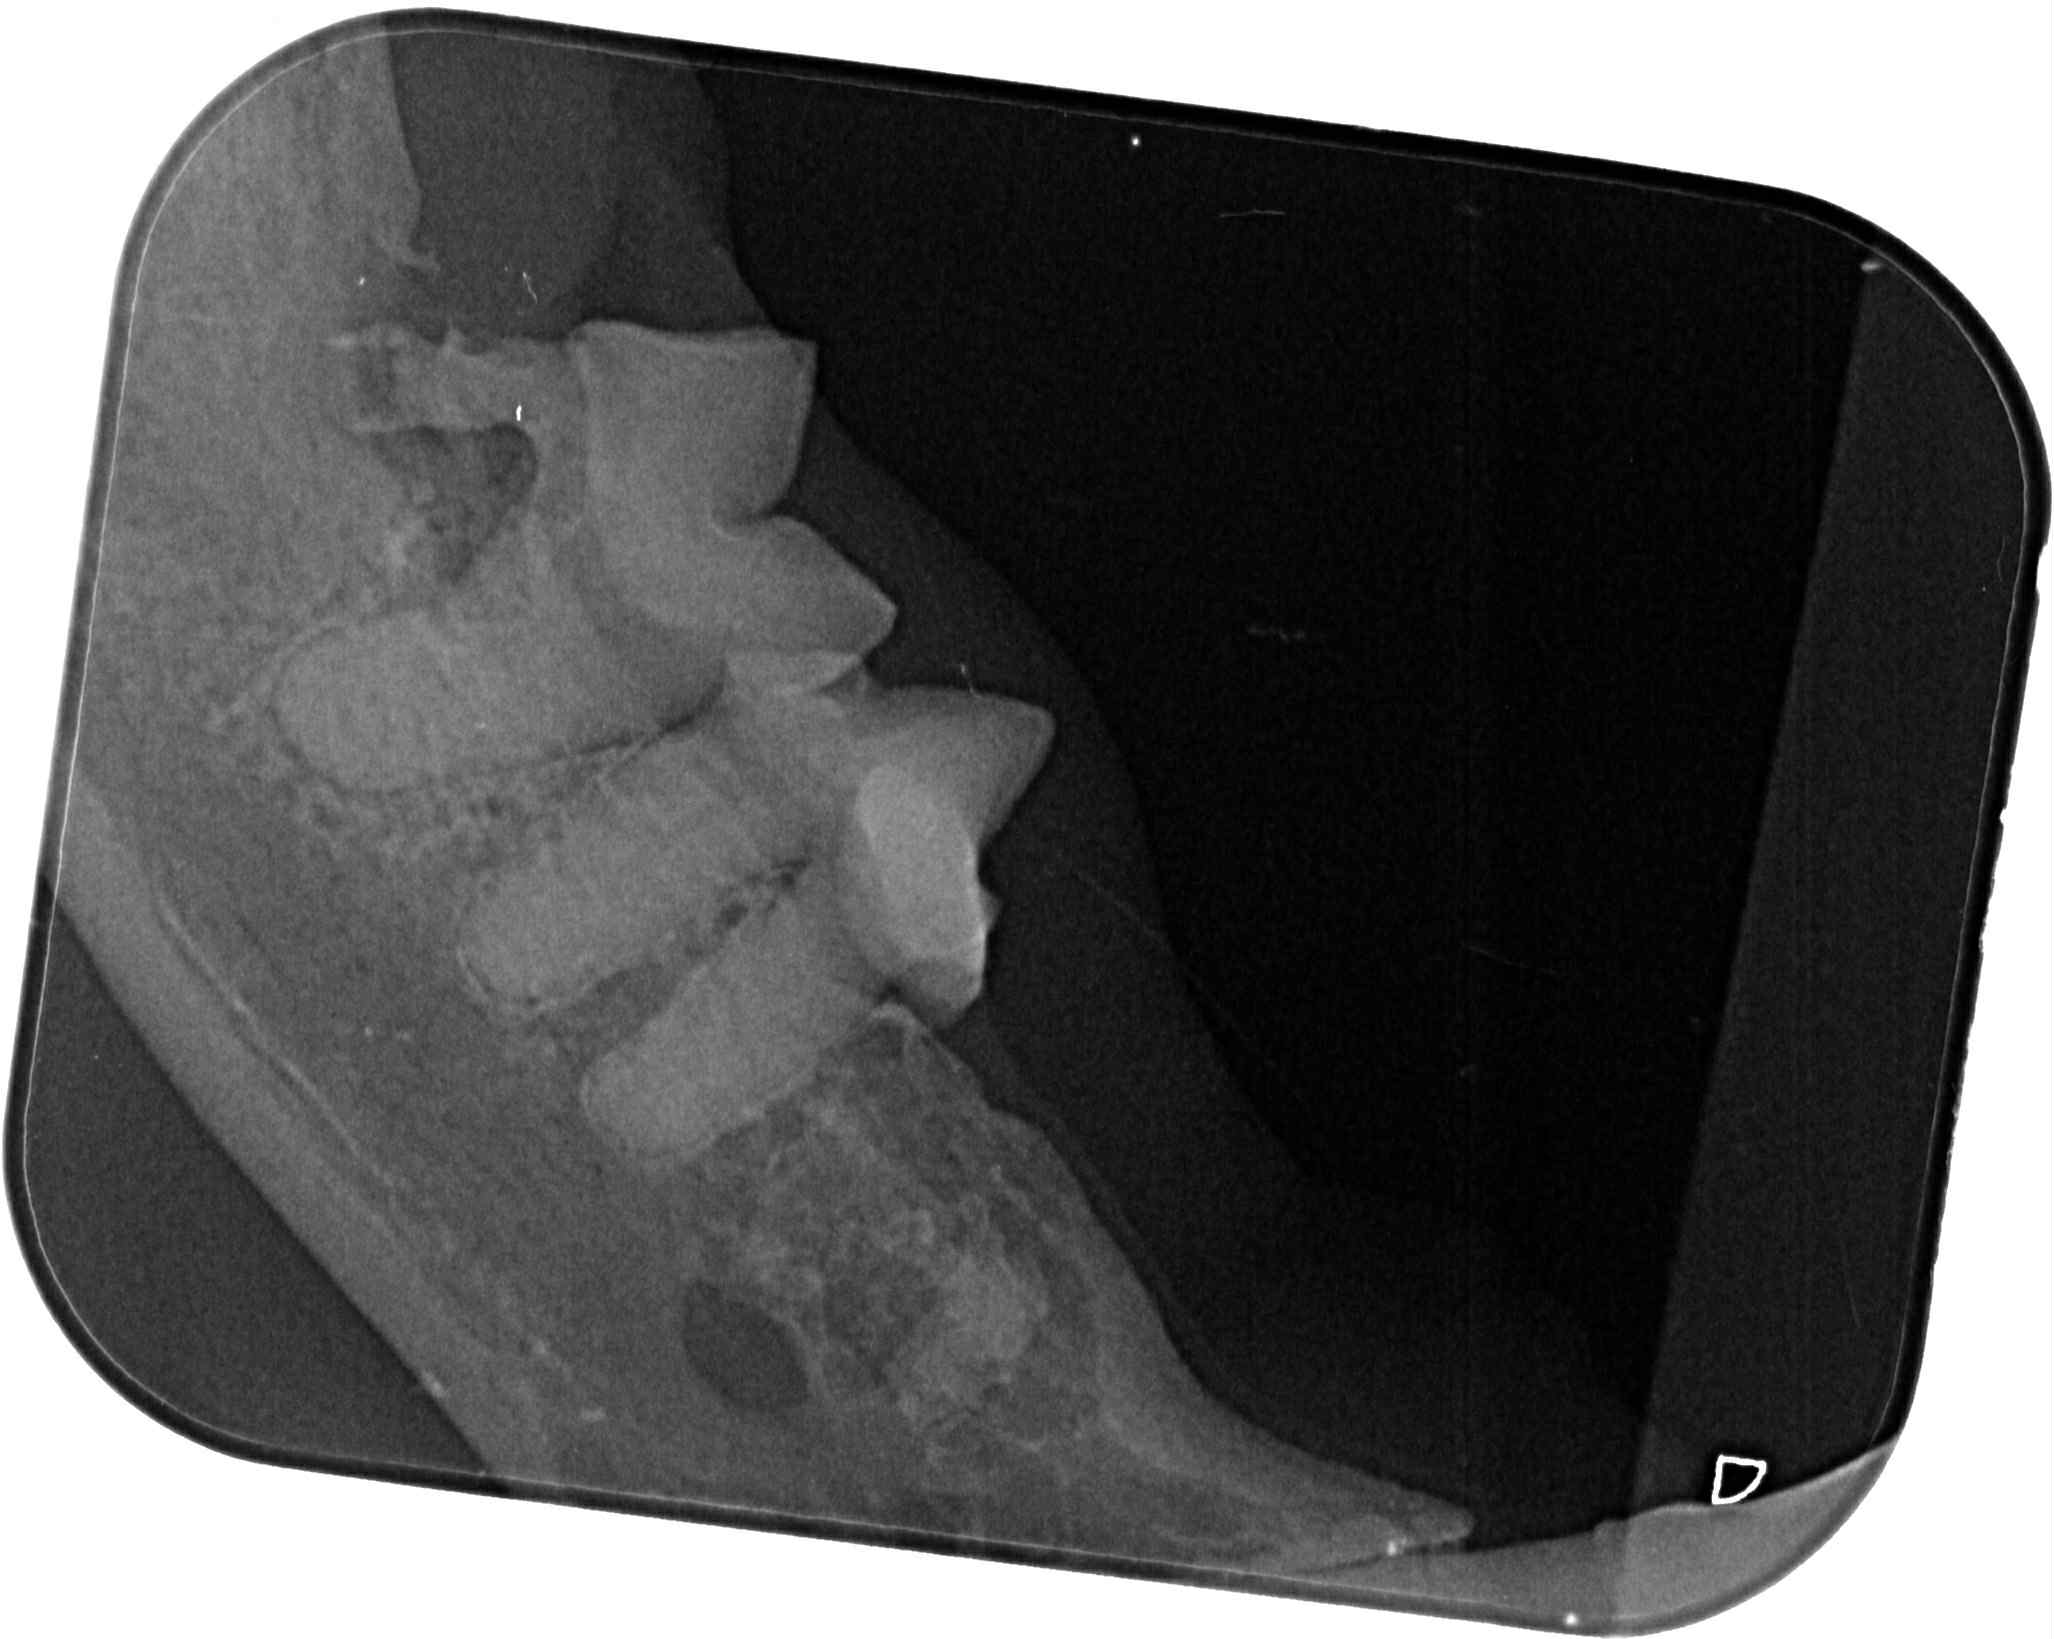

乖豹在安養之家受到良好照顧,身形越來越漂亮健美,看起來就是健康寶寶,但在2017年及2019、2020年間都突然出現無力站立、不願意走路、後肢肌肉看起來萎縮的情況,協會皆是安排乖豹至台大動物神經科專科看診,除了抽血檢驗、並將血液檢體送國外檢測重肌無力症、拍攝X光查看是否有腫瘤、核磁共振檢查及腦脊髓液採樣,查看是否腦脊髓發炎所造成的神經問題,但結果都沒有重肌無力症,也沒有找出確切原因,醫師懷疑可能是誤食含有有機磷的蟑螂藥,除了住院、吃類固醇、活性炭等用藥,照護員每天也數小時的為乖豹熱敷、按摩、復健,精神食慾有逐漸改善、走路慢慢恢復正常至痊癒,病癒後的乖豹又恢復平時的活潑調皮,在貓屋裡奔走玩耍。

原本是先讓乖豹再留在台北安養之家觀察一小段時間,希望確定健康無虞後,再讓他回到熟悉的大湖安養之家,但在2021年1月,照護員回報乖豹食慾體重都有漸降,1月23日呼吸看來急促,立刻約診沐恩醫院檢查,檢查結果,體溫40.3度,超音波及X光檢查發現胸腔有不明團塊及胸水,給予鎮定後抽出了有膿的胸水,當天辦理住院打泰寧抗生素針,醫師研判是嚴重的細菌感染和發炎造成膿胸,住院2天時,紅血球有持續降低的情況,血容比低到21,1月25日放置胸管引流、沖洗胸腔並引流膿水,每日都需要血檢及沖洗胸腔,在狀況嚴重會需要開胸手術移除胸腔中的膿包及清創,可能會需要輸血,幸好乖豹的食慾精神都有逐漸變好、血容比也有慢慢回升,至2月4日胸管沖洗出都已是乾淨的水,食慾精神也都穩定,醫師認為已可出院自行照護醫療,因治療剃掉肚子一大片毛的乖豹,讓大家很心疼,怕他冷為他穿上可愛又保暖的衣服,也每天準備好多好吃的罐罐幫他補身體,至2月17日回診的X光檢查,原本住院時胸腔有一大一小兩個團塊已經都不見了,這樣表示大團塊只是膿包,所以吃了抗生素就消失了,3月17日再回診,血檢結果都有很好的進步,體重也有回升,膿胸的危機已經解除,只要三個月後再回診拍X光及追蹤血檢即可。

原安置於苗栗貓屋的乖豹於2025年10月與其他貓咪全數移回台北安養之家後發現體型逐漸消瘦,且背上有一顆顆肉瘤以及牙齒有鬆動的狀況,於是安排2025年11月28日於沐恩看診,醫師表示整體狀況還不錯,背上粉瘤為良性,主要是牙結石嚴重,研判體重下滑應與此有關,需盡快安排牙周手術。後再於同年12月17日進行牙周手術,後面的臼齒、2顆下門牙及上顎那一顆不好犬齒都移除,保留下面兩顆犬齒,同時背部腫塊偏良性因此暫不切除。本筆醫助是自2025年11月28日至2025年12月17日間於沐恩醫院的費用,包含看診各項檢驗、牙周手術及用藥。

2025/12/17乖豹 沐恩牙周手術

一、看診說明

手術還算順利,血壓稍微比較不容易穩定,

目前後面的臼齒、2顆下門牙及上顎那一顆不好犬齒都移除了,

下面兩個犬齒的狀況還不錯,所以還是保留下,為了縮短麻醉時間。

皮膚的腫塊看起來外觀偏良性,所以沒切除。

目前看起來,他的咬合是比較正常的,

有可能不會咬到上顎,因為本來就已經有一邊沒有上門牙了,

理論上不會對生活有影響,另外他的下顎聯合原本就是鬆的,

所以會一個伸縮的彈性,對上顎影響相對減少

下顎聯合鬆的意思就是兩側下顎骨會些微的上下晃動。